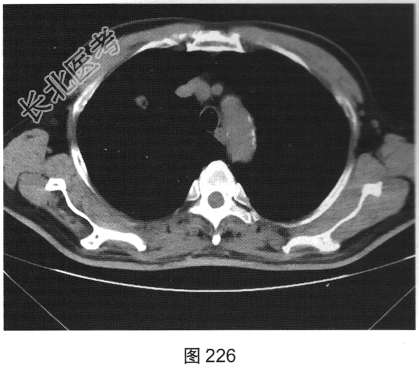

- [材料题] 患者女性,70岁。因“咳嗽、痰中带血3个月余”就诊。听诊无异常发现。胸部正侧位片发现右肺上叶类圆形小结节。

- 多项选择题2.[提示]患者行胸部CT检查,如图225、图226所示。该患者CT图像可见的阳性表现为( )

A、软组织密度结节

B、支气管充气征

C、毛刺征

D、空泡征

E、分叶征

F、棘状突起